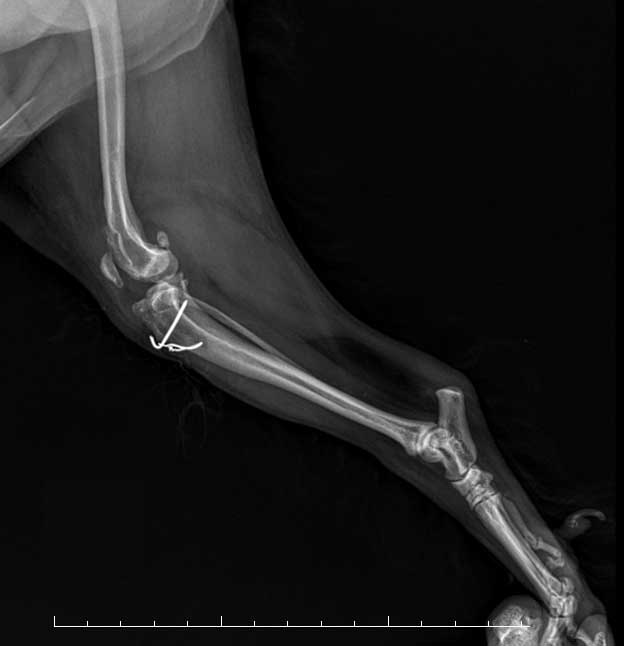

ECS 노령견 십자인대 수술기저 질환을 가지고 있는 노령견,

안정성을 더한 맞춤 수술 케이스 -